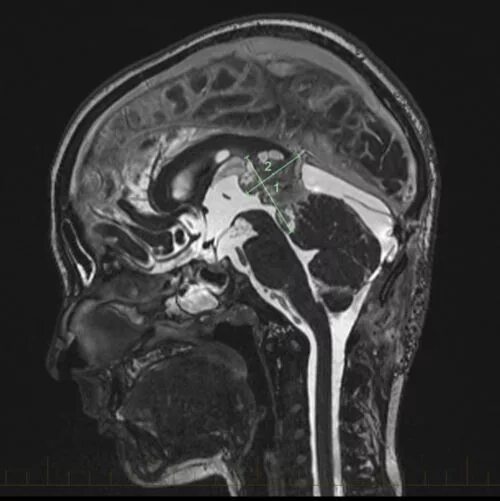

Бластома мозга